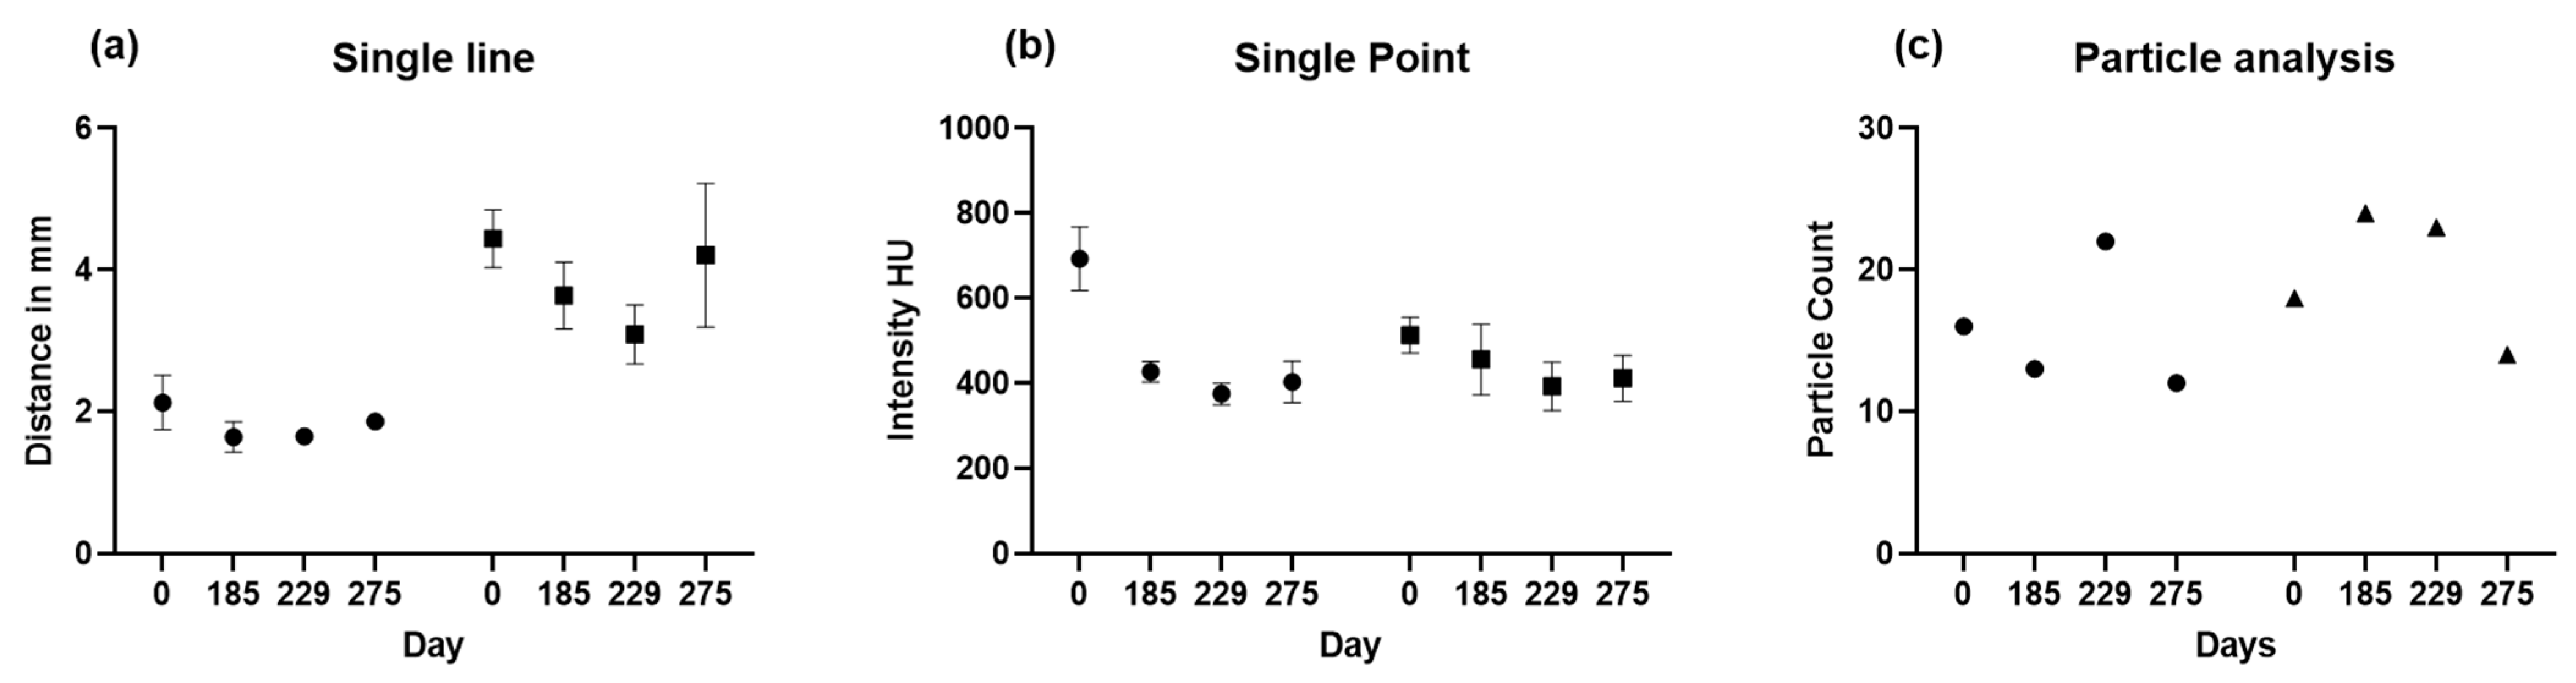

2.2.1. Two-Dimensional (2D) Measurement Methods

3.3. Two-Dimensional (2D) Measurements of Biparietal Thinning

3.5. Comparisons of Changes in Bone Loss over Time